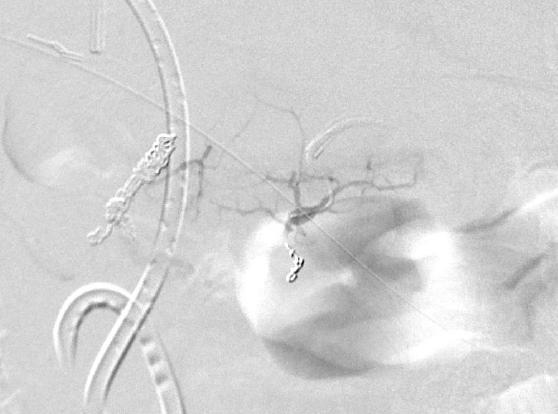

腹腔 动脉造影发现造影剂外溢,但供血动脉似乎来自于胃十二指肠动脉,但不确定 |

超选择胃十二指肠动脉显示出血的动脉来自于胃十二指肠动脉的一个细小的未命名动脉分支 |

弹簧栓子阻塞胃十二指肠动脉后造影 |

选择性胰背动脉造影未发现明显出血 |